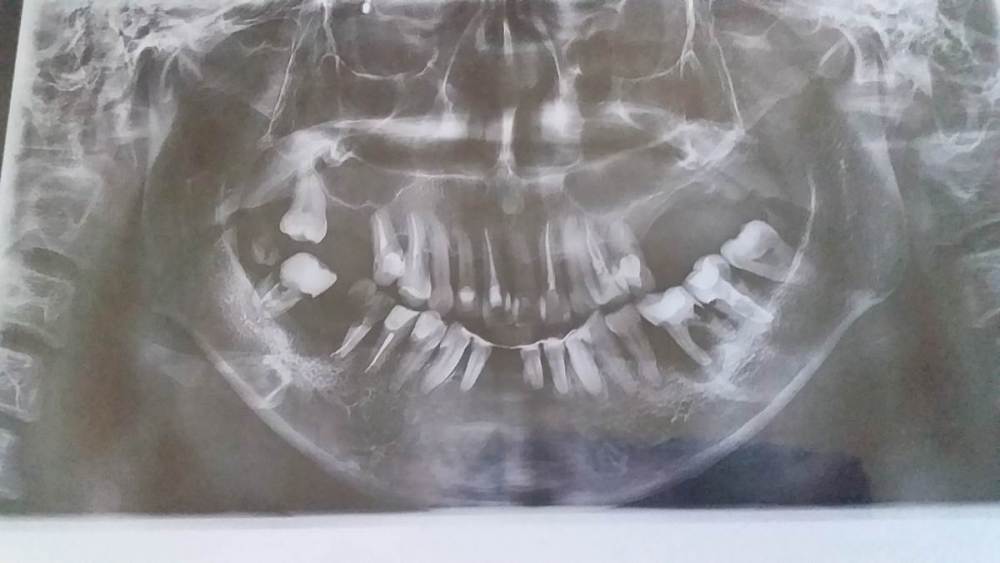

Гузяль Опубликовано 1 июня, 2022 Поделиться Опубликовано 1 июня, 2022 Здравствуйте, уважаемые стоматологи. У меня был диагностирован парадонтит 5 лет назад в частной клинике. Там же его стали лечить, сказали приходить каждые полгода Проводили чистку, ставили уколы, мазали пастой. В итоге по семейным проблемам, 2 года не ходила на лечение. За это время ситуация во рту кардинально поменялась. Шинированные нижние зубы передние выпали, наверху слева не осталось жевательных зубов, такая ситуация и с нижней челюстью. Врачи предлагают удалить оставшиеся зубы и поставить зубные протезы. Не могу спокойно жить, уже не смотрю на себя в зеркало, впала в депрессию. Посоветуйте, неужели всё больше ничего нельзя сделать? В Ссылка на комментарий

red_butler Опубликовано 1 июня, 2022 Поделиться Опубликовано 1 июня, 2022 прогноз зубов плохой 2 1 Ссылка на комментарий

Doc Опубликовано 1 июня, 2022 Поделиться Опубликовано 1 июня, 2022 Ну, сейчас уже поздно плакать и каяться. Нужно решать проблему. Вопрос только в том, как ее решать. Если собираются делать два полных съемных протеза в 33 года, то это, конечно, плохой вариант. Если грамотное несъемное протезирование на имплантатах, то можно сделать так, что на качестве жизни это никак не отобразится. 1 1 Ссылка на комментарий